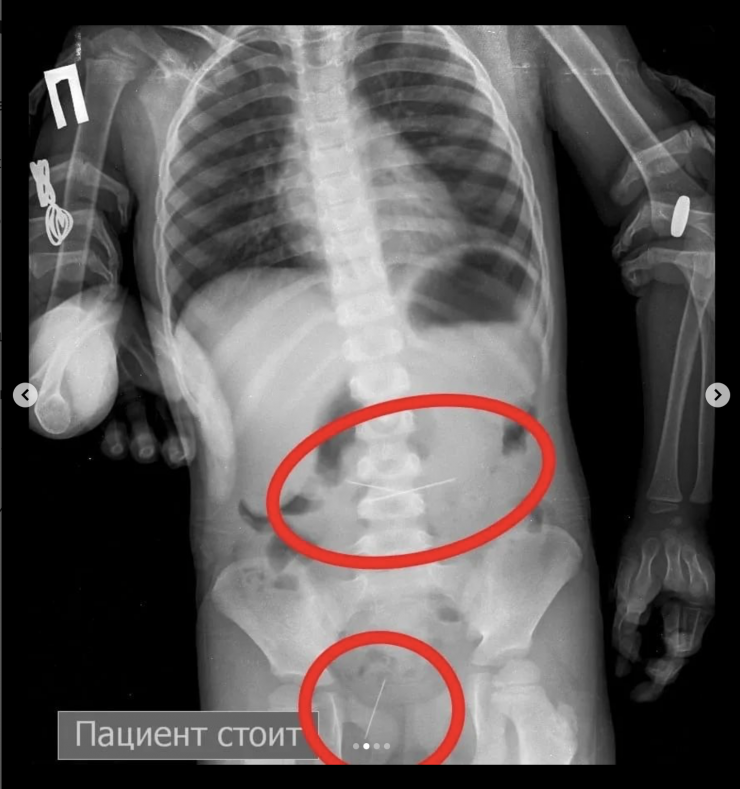

"Позже на контрольной R–грамме брюшной полости обнаружены еще две иглы в верхнем этапе брюшной полости и одна игла в проекции таза. Проведена повторная ЭФГДС, и удалена игла из желудка. Затем при помощи колоноскопии удалена игла, зафиксированная в сигмовидной кишке", - сообщил врач-хирург высшей категории Сейдахмет Чинибеков.

Однако после этого в ходе наблюдения ребенка на контрольной R–грамме брюшной полости обнаружена еще и четвертая игла в проекции таза.